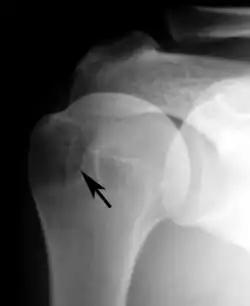

proximal humeral pseudocyst

Plain x-rays of the shoulder may show a “proximal humeral pseudocyst”. This localized area of bone atrophy is the result of increased blood circulation which demineralizes the bone at the attachment of the rotator cuff tendon. It is evidence of chronic inflammation of the rotator cuff. Chronic shoulder inflammation is frequently asymptomatic, and this cystic appearance may be the only evidence of an inflammation.[22][23]